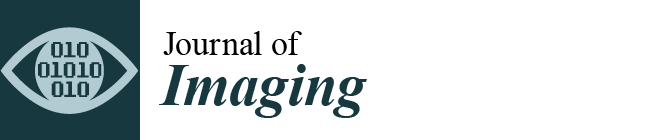

2.2. Imaging

2.3. Postprocessing

3. Results